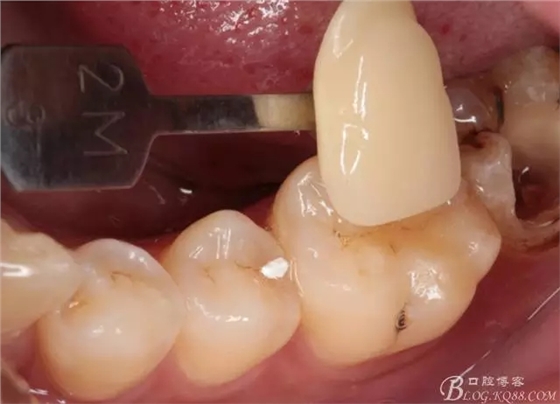

去除暫封物,拍照,比色。

流動(dòng)樹脂充填窩洞,金霸王車針和鎢鋼車針常規(guī)備牙,配合硅膠尖拋光,頰側(cè)排00排齦線。硅橡膠二次法取模,記錄咬頜關(guān)系,臨時(shí)樹脂充填窩洞。